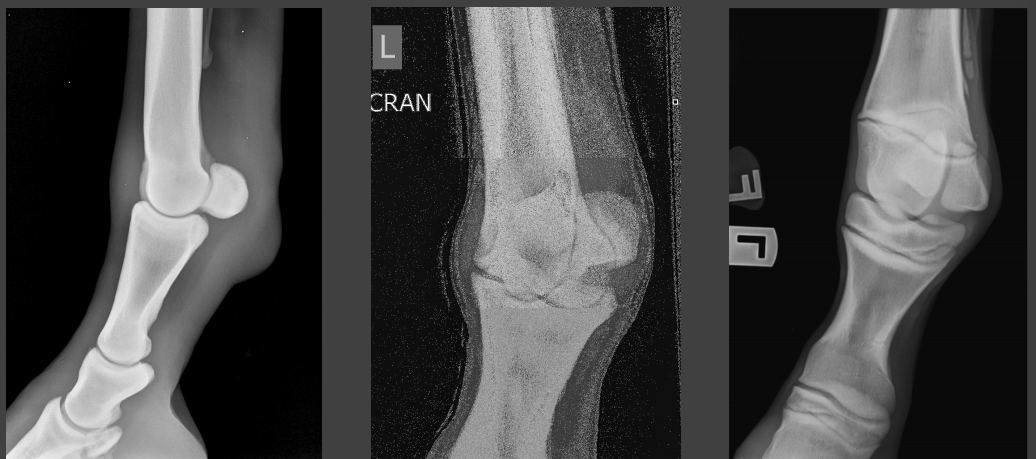

Q

fetlock radiography

A

1 lateral of the metacarpophalangeal joint with proximal sesamoid is not enough because the sesamoid obscures the carpal bones.

you need a couple more oblique images.